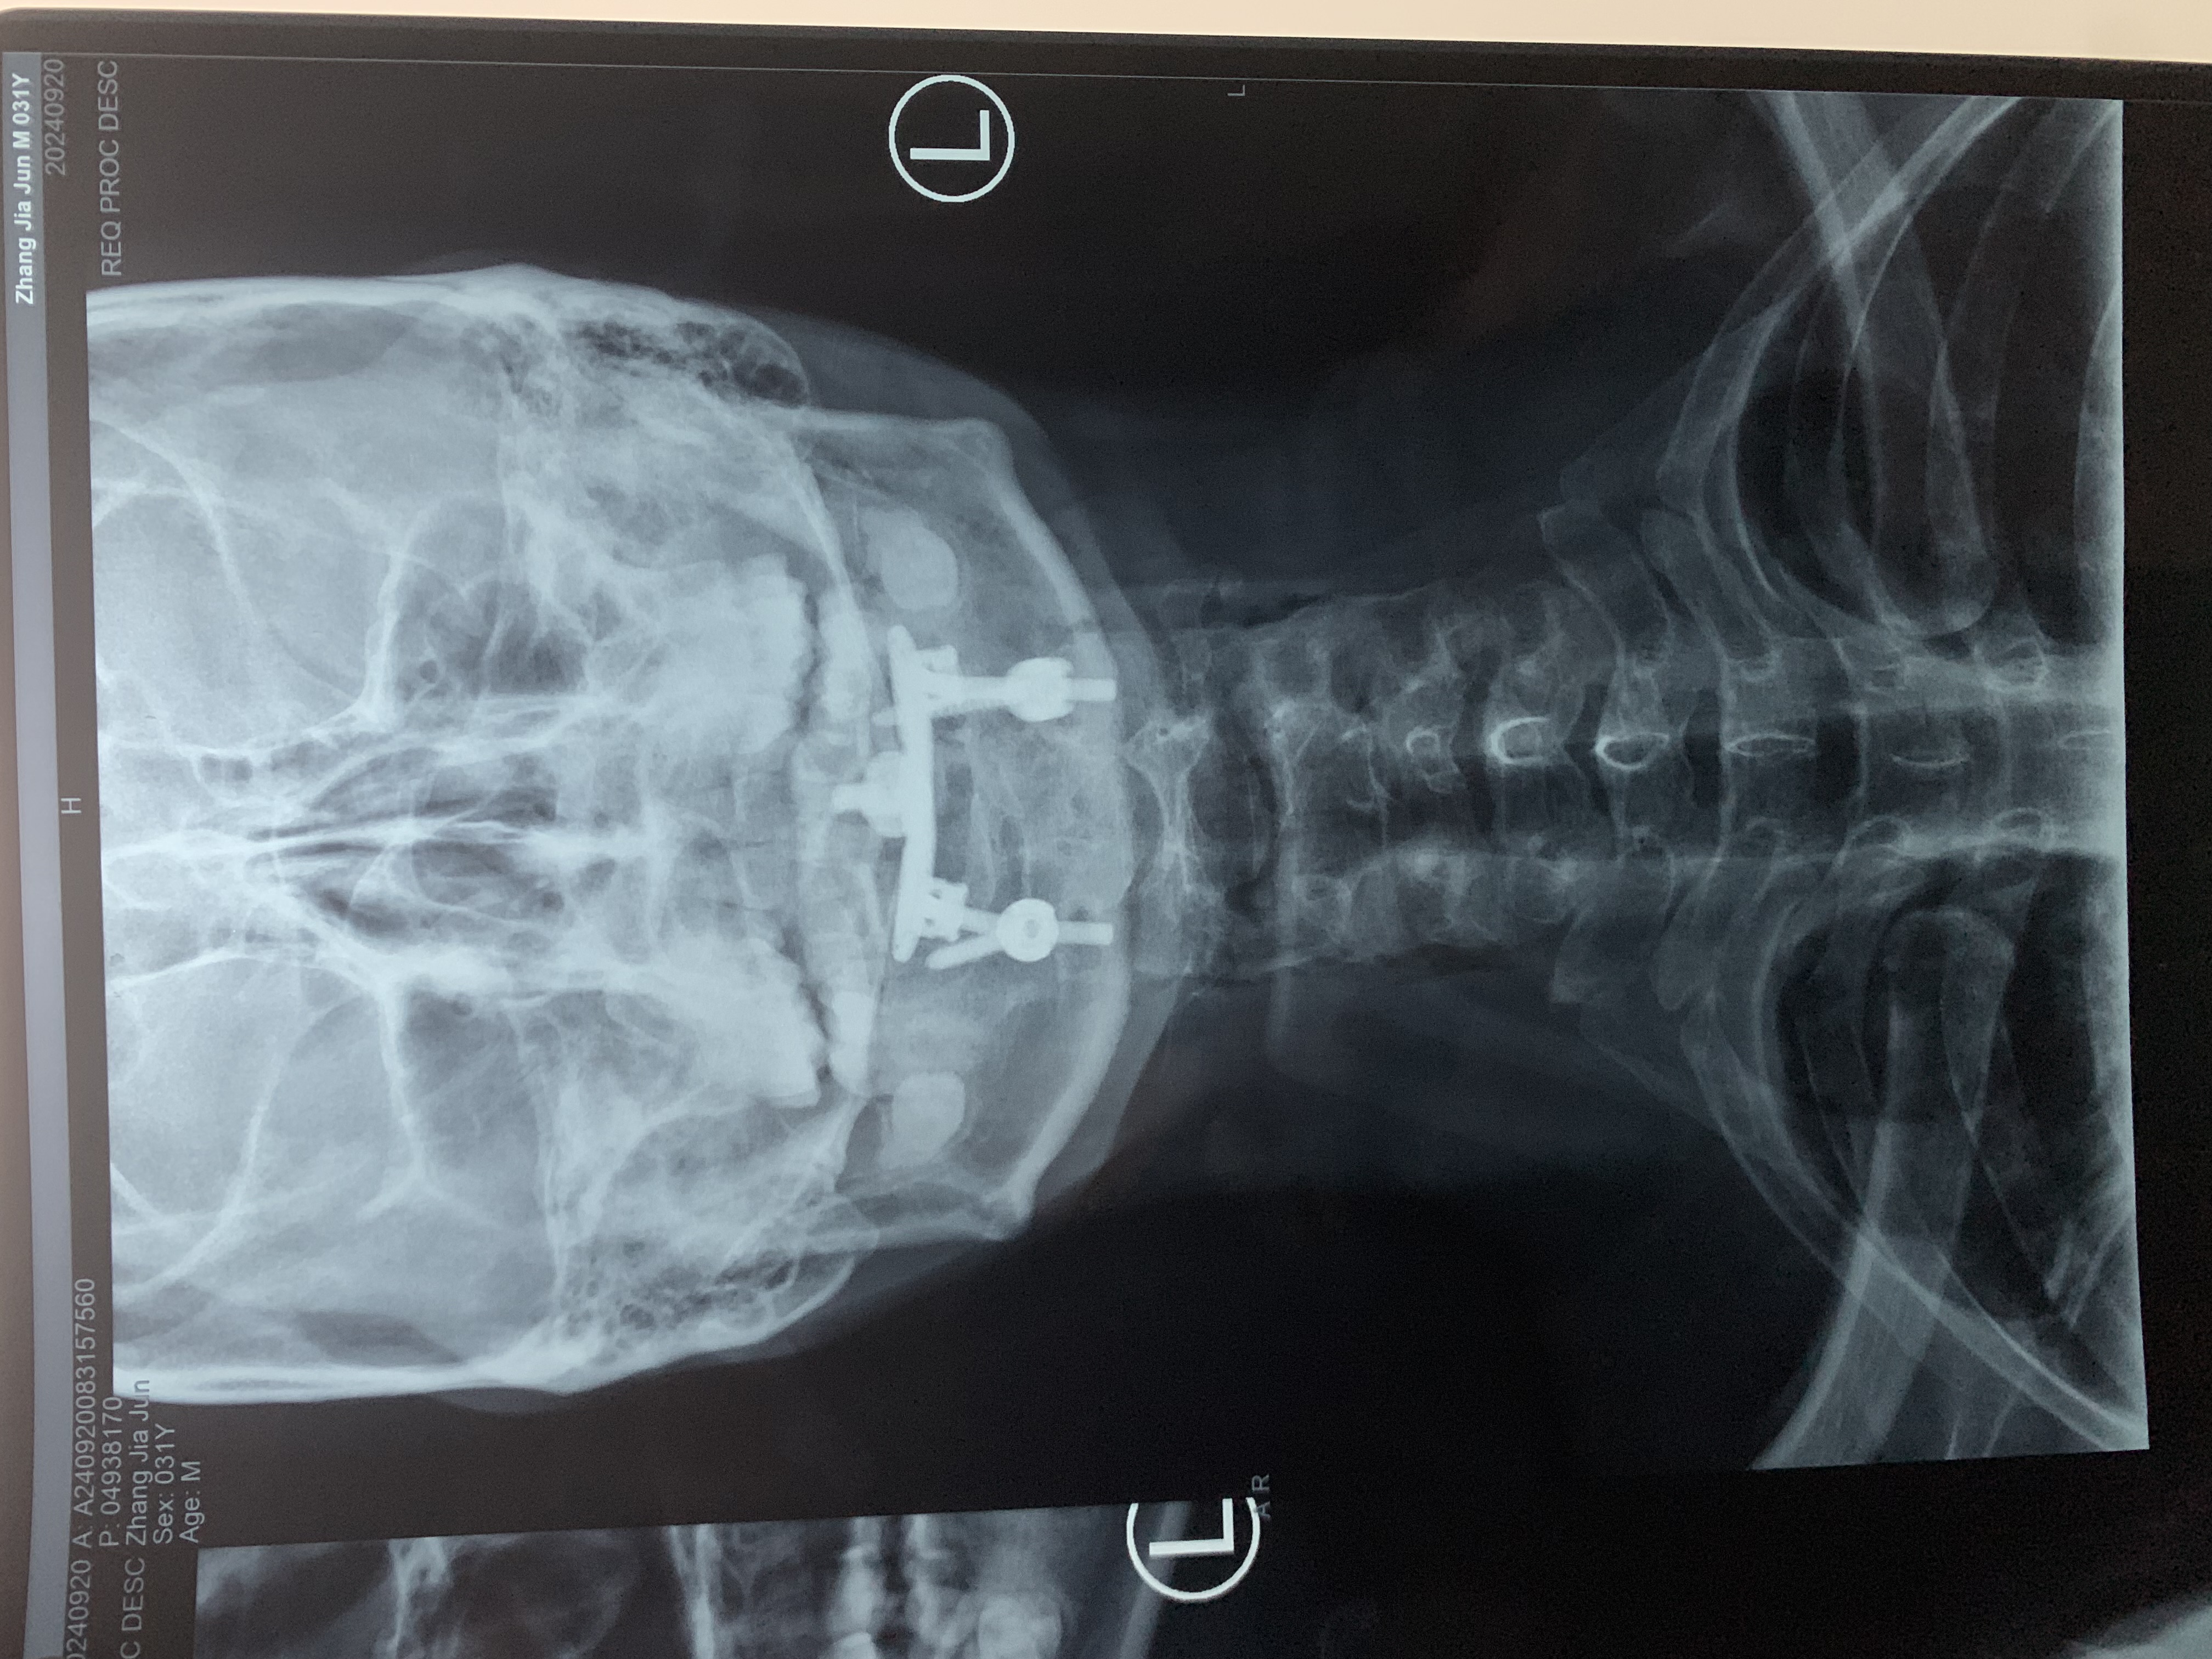

• 术后影像: